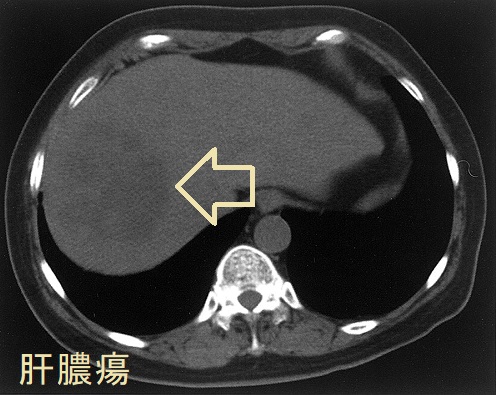

肝膿瘍の症状は発熱、右季肋部痛などで、肝腫大、肝叩打痛を認めます。

肝膿瘍と同側の甲状腺膿瘍を伴うレミエール症候群をおこし、甲状腺半葉切除術を行った報告があります(Eur J Clin Microbiol Infect Dis. 2004 Jul;23(7):570-2.)。